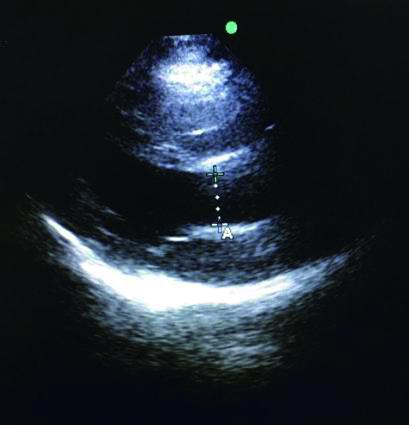

充分暴露前胸部,于胸骨旁长轴切面,选取主动脉瓣根部测量左室流出道直径与截面积。选取心尖五腔心切面,通过脉冲多普勒测量动脉流速,计算左心室流出道收缩高峰期的流速时间指数,测量心率,最后通过心脏检查软件包自动计算出CO(图 3、4)。通过上述PLR试验,联合超声获得的CO,最后计算ΔCO值,ΔCO≥15%定义为容量反应性阳性;反之为容量反应性阴性。

|

| 图 3 胸骨旁长轴主动脉根部 Figure 3 The aortic root at parasternal long axis |

|

|